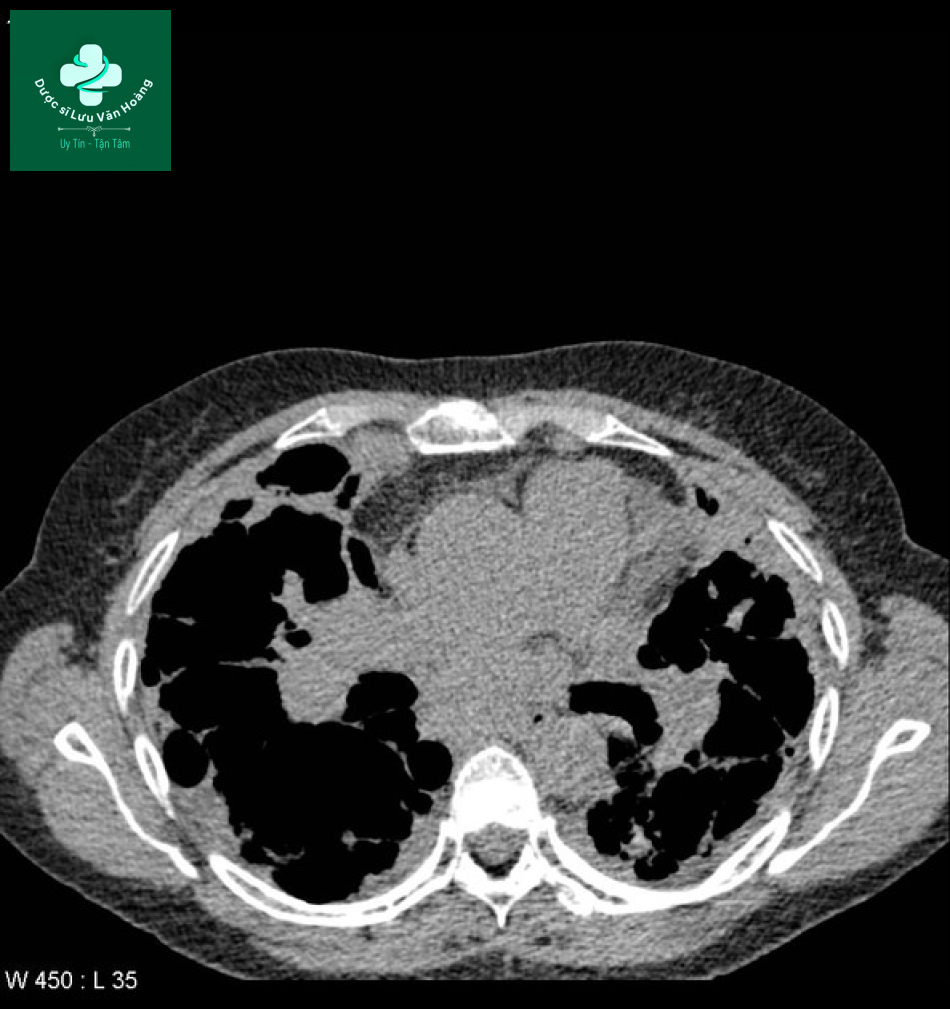

Case 3: giai đoạn IV

- Phim x-quang cho thấy các dải xơ phổi và hạch trung thất.

- Phim CT:

- Khí phế thũng vùng đỉnh với các kén khí thành mỏng

- Các dải xơ ở vùng giữa và dưới hai phổi

- Giãn phế quản thùy dưới hai bên

- Các nốt nhỏ ở thùy dưới

- Hình ảnh kính mờ ở thùy lưỡi

- Dày màng phổi vùng đáy

- Hạch bệnh lý: quanh mạch máu, cạnh phải khí quản.